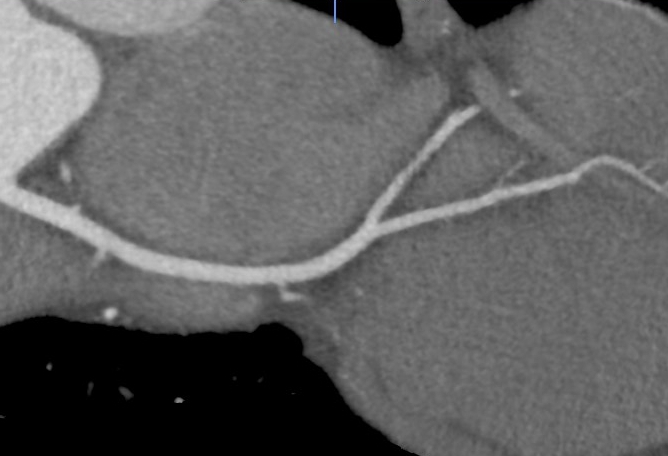

Full training to use Coronary CT software, no prior experience required

Drs Kon and Marjoram will demonstrate cases and teach you to use Vitrea software